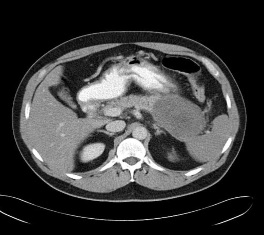

脾动脉瘤栓塞技术的基本要点 栓塞前最重要的是CTA的检查,以利于脾动脉瘤的治疗计划的制定。CTA可以发现脾动脉瘤载瘤动脉的大小和走行(和导管的选择相关),脾动脉瘤的位置和大小,脾动脉瘤的类型(和选择栓塞方式相关)以及脾动脉瘤伴发病症的。术前必备6~8F的弯曲的引导导管,主要用于稳定工作导管,为释放各种栓塞器械或栓塞剂做准备。同时需要准备Cobra 或 各种适形弯曲导管作为工作导管,其经过引导导管进入载瘤动脉。各种亲水导丝,超长和超硬亲水导丝,以备一旦需要置换各种需要的工作的导管。微导管主要用于困难的病例。事实上,在大多数情况下微导管的应用使原本困难的病例变得容易。围手术期广谱抗菌素的应用。作为血管内的异物,栓塞部位一旦发生感染后果非常严重。 弹簧栓子栓塞技术(Coil embolization) Trapping 技术:又称为sandwich技术(三明治技术)和backdoor-frontdoor技术(前后门技术)。是最为常用的脾动脉瘤栓塞技术。在微导管技术的支持下最适合超选择末梢动脉瘤的栓塞,宽颈和大动脉瘤的栓塞治疗。主要缺点是可以造成脾和部分脾梗死,但一旦栓塞技术成功,再通的机会罕见